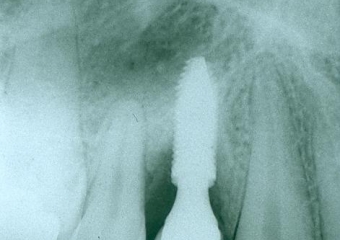

Raio X da prótese fixa de porcelana sobre o implante